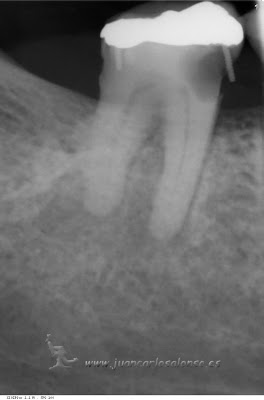

Paciente con cirugía programada para la extracción de los cuatro incisivos inferiores e injerto oseo por presentar un gran quiste a nivel mentoniano. acude a consulta demandando una segunda opinión. las pruebas de vitalidad dan como resultado qué solo el 42 está afectado. se propone ,y acepta, como tratamiento desvitalización del incisivo lateral inferior derecho